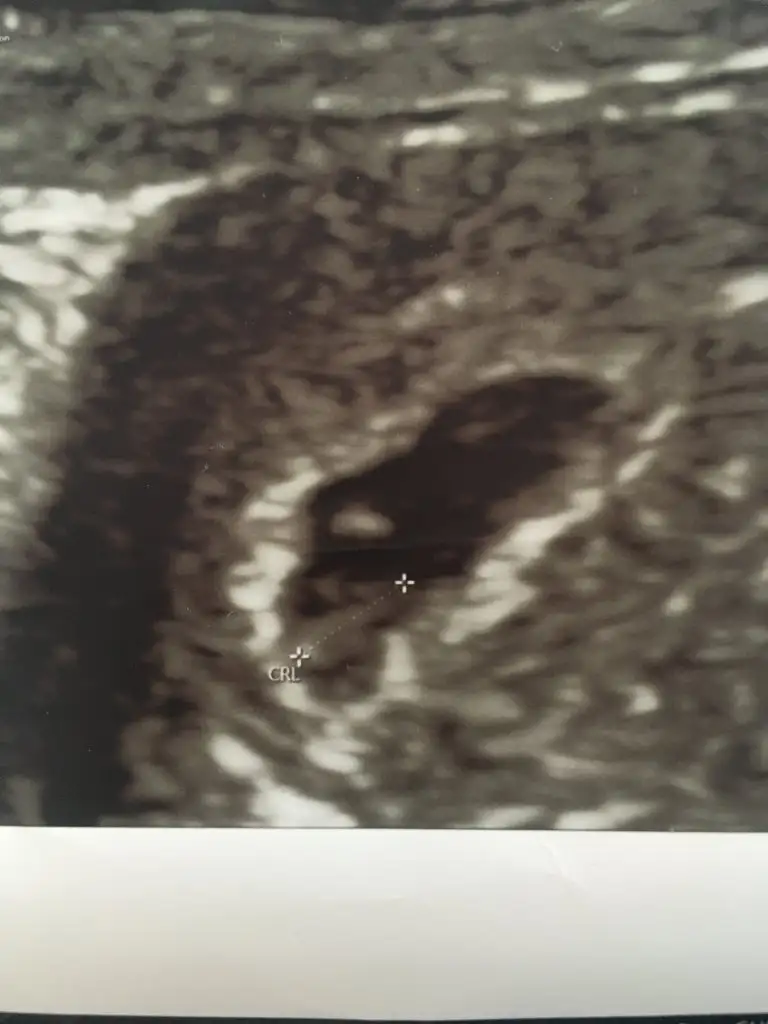

Ramzi teorisine göre cinsiyet tahmini yapacagim ilk ultrasyon resminizi atin bakiyim. Eger cinsiyetiniz belliyse hic söylemeeyin bakalm dogru tahmin edebilecekmiyim daha dogrusu ramzi teorisi hakli cikacak mi?

Cinsiyet erkek mi tatlimkarından 6+1 ultrason yorum alabilir miyim ?

Tatlim karindansa muayene erkek cinsiyeti çok eminim vajinal muayeneyse kiz çok belli ultrason ..cinsiyeti öğrenince yazar misinYorumlayabilir misiniz ?

Tatlim karindansa muayene erkek cinsiyeti çok eminim vajinal muayeneyse kiz çok belli ultrason ..cinsiyeti öğrenince yazar misin